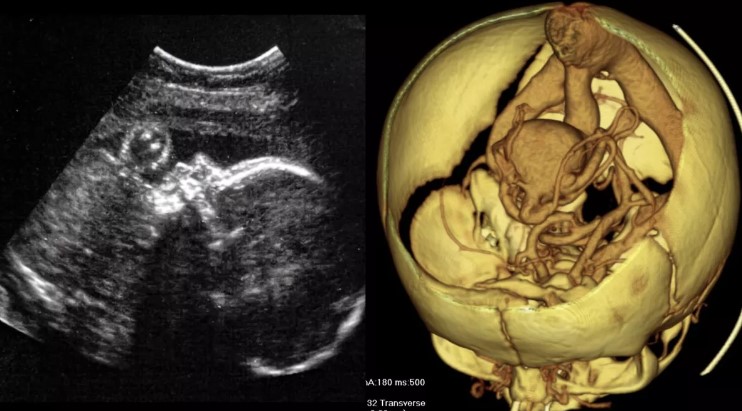

A baby’s brain blood artery malformation was surgically fixed while still in the womb for the first time ever! The…